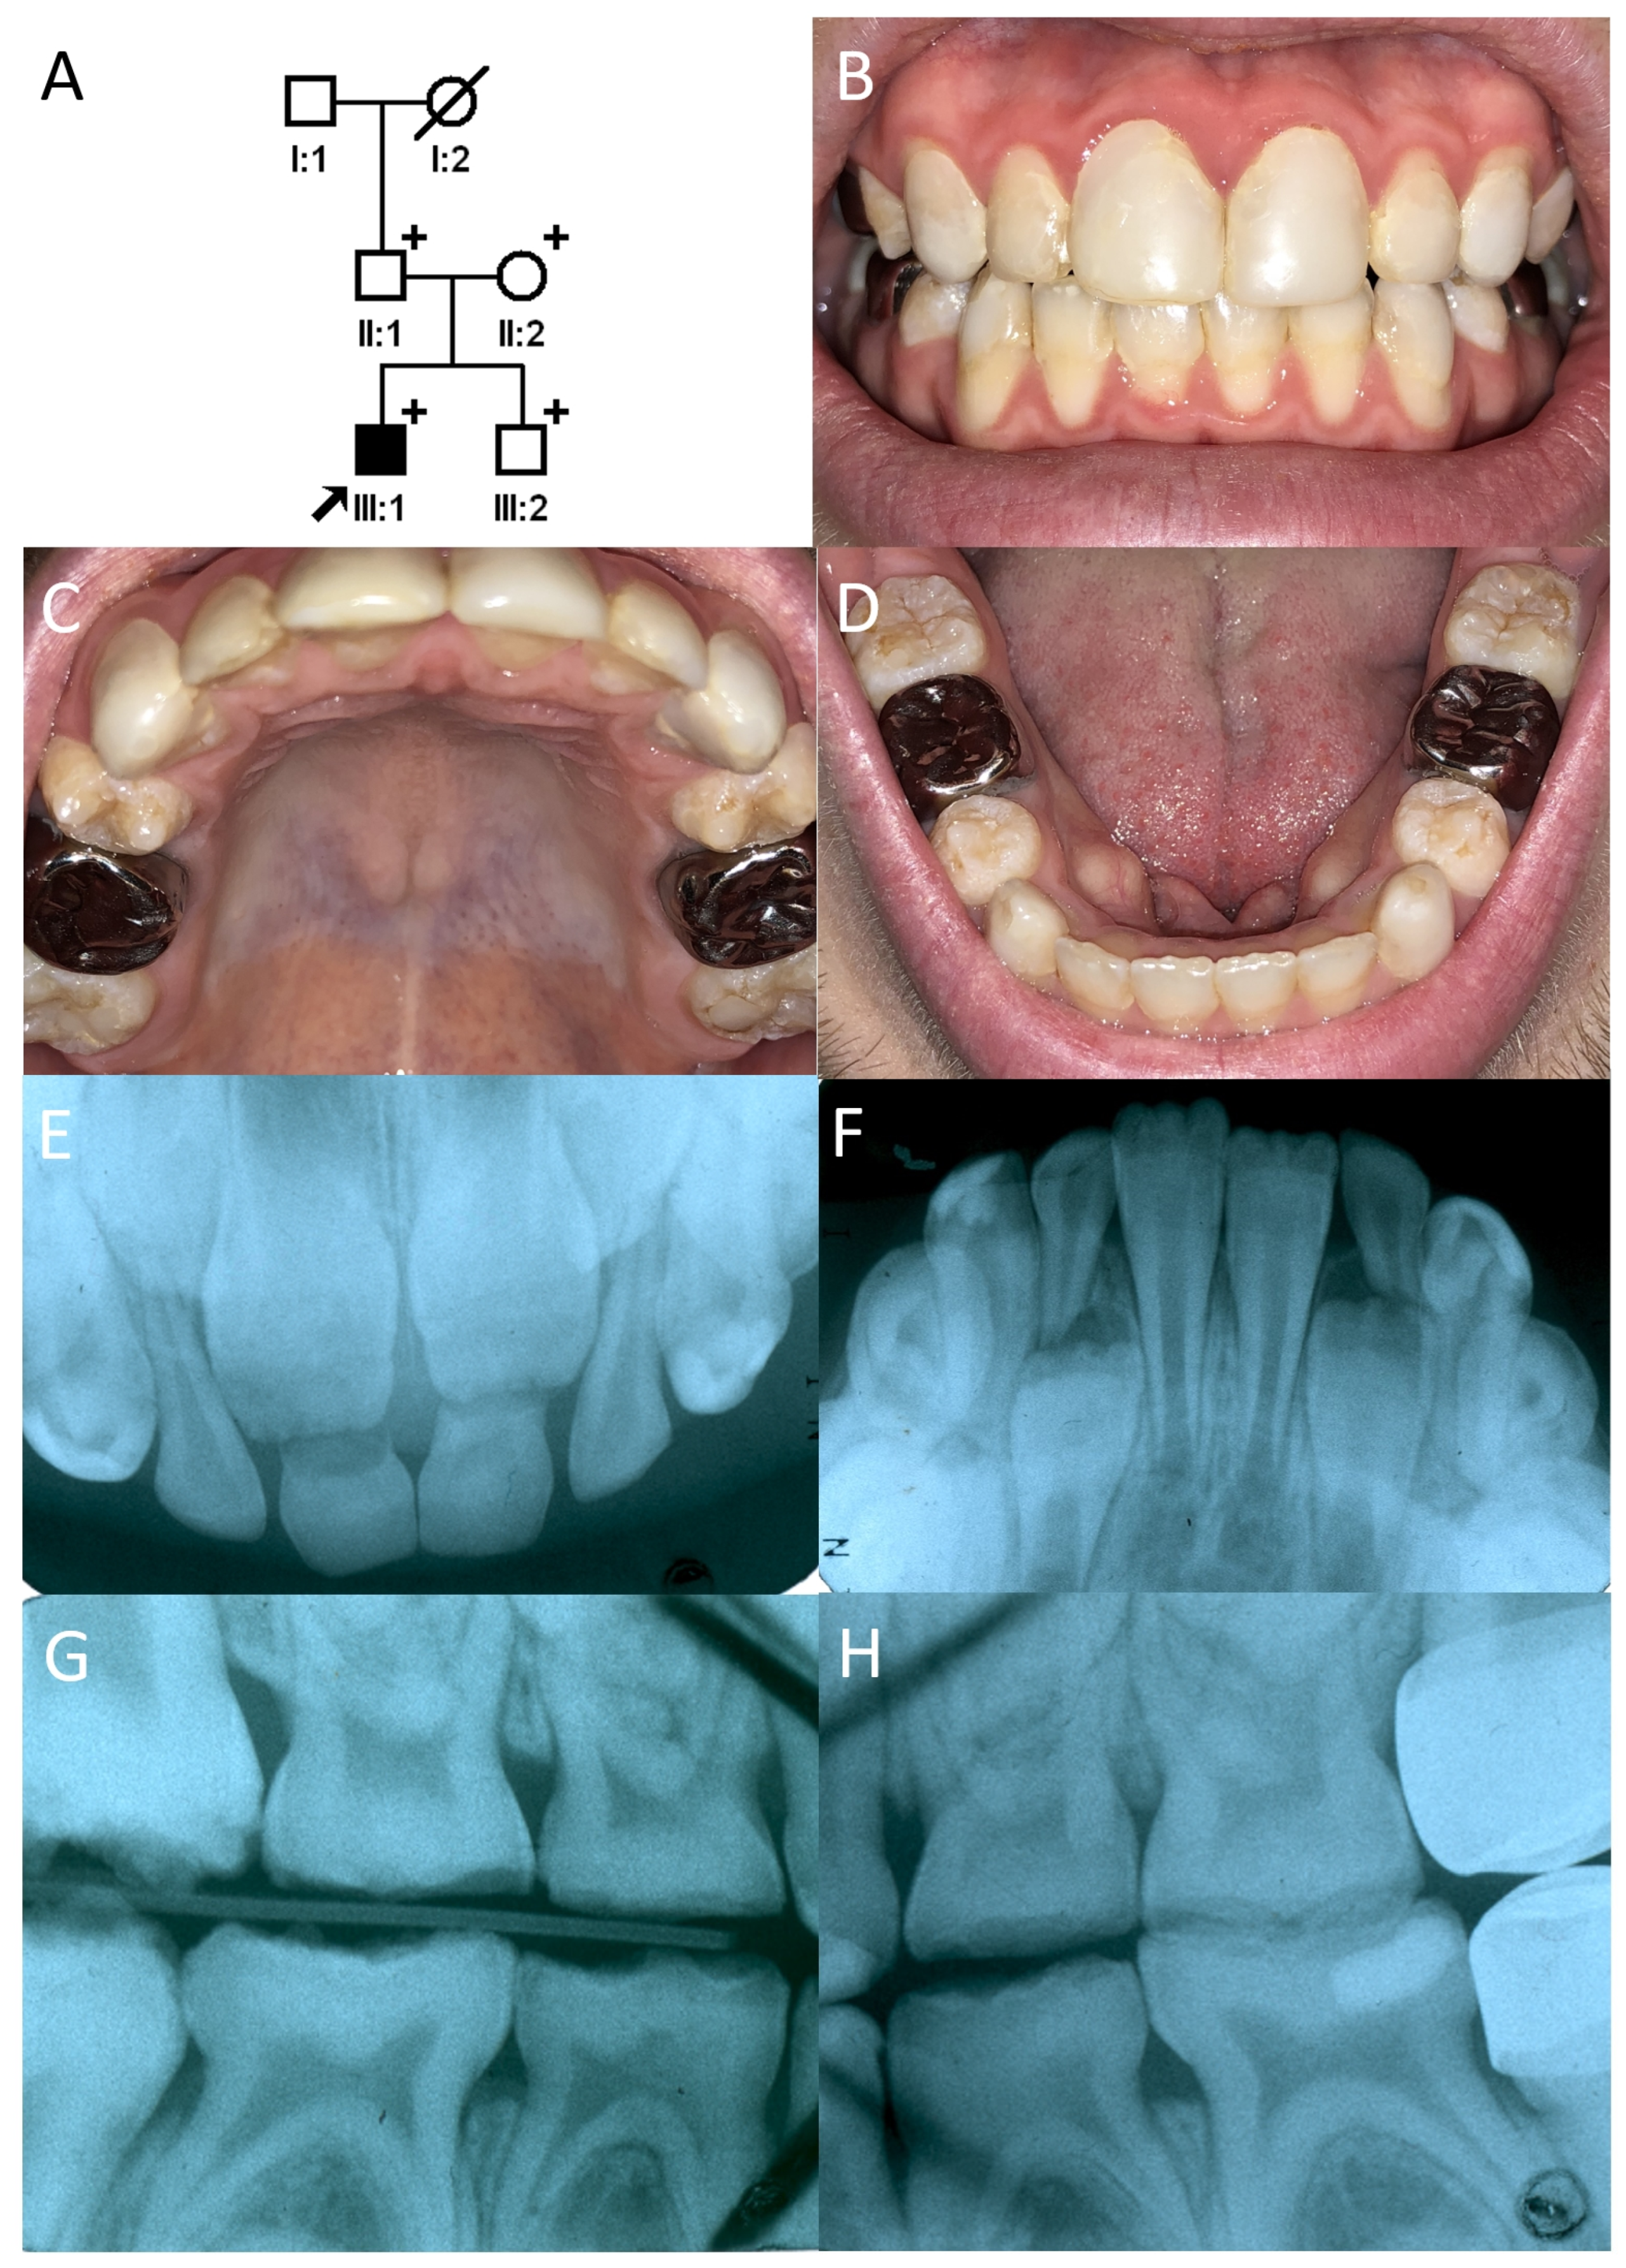

3.2. Family 2